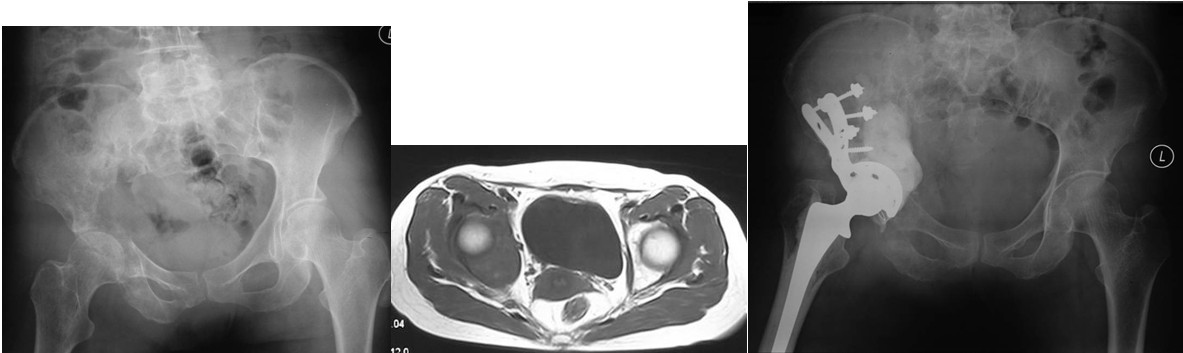

Ⅲ型:髋臼内壁、顶部及外侧壁均破坏。仅使用带翼网杯的全髋假体是不够的。在这种情况下,需要在骨盆缺损处放置数根斯氏针以便于将位于解剖位置的髋臼假体所承受的应力传导至脊柱(1-3)。在大多数髋臼周围破坏广泛的病例,需要采用扩大的髂股骨切口入路,以便于探查骨盆内外侧区域。在显露清楚后,自髋臼缺损处沿残留的正常髂骨向骶髂关节方向钻入2-3根斯氏针,并越过关节达到骶骨。应采用较粗的斯氏针,术中还需要X线监测以保证斯氏针的位置。在钻入斯氏针的同时,应用手指触摸坐骨切迹,以保证斯氏针的方向,防止其穿入骨盆内壁。当髋臼缺损较大时,还可以自前部髂嵴向前柱的耻骨及后柱的坐骨钻入更多的斯氏针做进一步的加强。在髋臼假体顶部切断斯氏针,并安装带翼网杯,在髋臼深部可以用金属钛网加强骨水泥固定。术后病人可全部负重行走,但需置患肢外展中立位约4周时间以防止脱位。也有采用马鞍式假体置换的报道, Benevenia等对20例髋臼III型转移瘤患者进行了马鞍假体置换,术后MSTS 93评分平均16.6分,多数病人可以扶拐行走(5)。对于髋臼上壁及内、外侧壁均破坏的HarringtonIII型患者,本组病例中,有7例患者采用了肿瘤刮除后、于骶髂关节处植入3-4枚斯氏针, 骨水泥填充髋臼上壁骨缺损,水泥型全髋重建髋关节。其中,有2例患者出现下地后髋部痛疼,负重时髋部不稳定。考虑为负重时骶骨内斯氏针承受较大剪力, 出现髋关节不稳。因此,在本组病例中,我们对4例Ⅲ型患者实施了整块切除、可调式人工半骨盆置换术。术后6周患者可以扶拐下地行走。平均MSTS93评分为23.3分。

Ⅳ型:为了达到治愈而需要进行整块的髋臼切除。对于部分单一髋臼转移的病例,以及髋臼周围骨质破坏范围较大的病变,在广泛切除肿瘤后,重建髋关节(内半盆切除)有时较为困难。在这些病例,可以选择马鞍式假体。这种方法最开始用于全髋关节置换术后的骨缺损,后来也用于原发或转移性髋臼肿瘤的治疗。也可以选用带有固定翼,能固定于残存髂骨和耻骨支的定制型髋臼假体(7-9)。这种假体制作前通常需要进行CT模拟重建设计。固定方式常用螺丝钉和骨水泥。有时想要应用定制型假体达到理想的固定位置较为困难。对于骨盆环的完整性重建,纵向稳定是极其重要的,同时要考虑人工假体在术中的可操作性。定制型骨盆假体为非组配式,其髂骨固定螺钉是单轴向的,不能根据术中截骨情况调整假体,固定也不够牢固。 我们设计使用的可调式半骨盆假体,其髂骨固定钉改为双轴向或多轴向固定,假体与骨之间的界面为垂直压力、而非剪力,增加了稳定性,同时可以根据髂骨截骨的高度选择颈长的臼杯,利于安装和保持骨盆平衡(10)。组配式骨盆假体还考虑到骨盆纵向和侧方的稳定因素, 尽量达到恢复骨盆环连续性和稳定性的目的。对于髂骨区和髋臼上缘的骨缺损重建,钉棒系统简单,易于操作,但固定钉在骨内的应力较大,容易在负重的情况下对骨质产生切割,尤其骨质疏松的病人固定更加不稳,因此需用骨水泥加强。由于组配式人工骨盆是一个组合装置,因而体积较小,便于软组织覆盖,伤口感染率大大下降。

图4,女,52岁,乳腺癌髋臼转移, Harrington III型

图5,男,69岁,肾癌髋臼转移, Harrington IV型